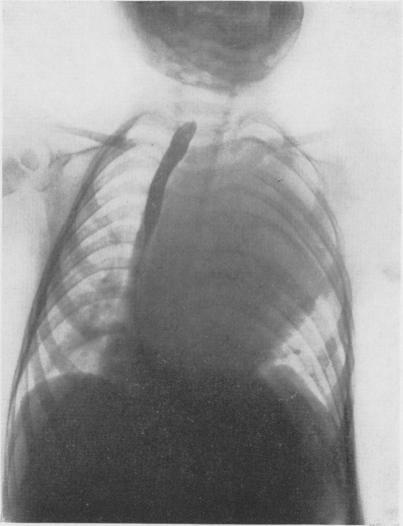

Intrathoracic neurogenic tumors in infants and children; a study of forty cases.

Ann Surg. 1959 Jul;150(1):29-41. doi: 10.1097/00000658-195907000-00003.